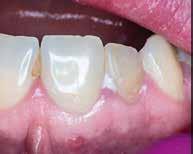

4. a–b. ábra: A reszorbciós üreg Biodentine-nel való feltöltése. Intraoperatív (a) és radiológiai felvétel (b). – 5. ábra: Az öt hónappal később látható állapot. Nem észlelhetők gyulladás fennállására utaló jelek.

A gyökértömés elkészítése során meleg vertikális kompakciós technikát alkalmaztunk, sealerként pedig CeraSeal-t (Meta Biomed; 3. ábra) használtunk. A reszorbciós üreget Biodentine-nel (Septodont; 4. a–b ábra) töltöttük fel. A reszorbcióval érintett területtől koronális irányba elhelyezkedő csatornaszakaszt pedig tisztán meleg guttaperchával kezeltük. Ezt követően a lebenyszéleket visszafektettük, és varratok behelyezésével eredeti pozíciójuknak megfelelően rögzítettük. A koronai részt kompozit tömőanyag segítségével állítottuk helyre. Kontrollvizsgálatra 5, illetve 30 hónappal később került sor (5. ábra). A csontos telődés jelei már 5 hónap után észlelhetők voltak (6. a–c ábra). A 30 hónappal később végzett kontroll során sem találtunk csontban lévő lézióra, törésre vagy egyéb pathológiás elváltozásra utaló jeleket (7. a–b ábra)